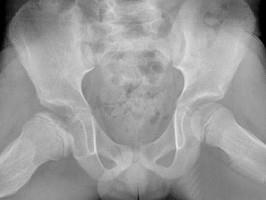

问题 男,6岁,髋痛、跛行,请结合CR检查,选出最可能的诊断 ( )

选项 A、骨囊肿 B、软骨肉瘤 C、股骨头骨骺缺血坏死 D、骨肉瘤 E、髋关节结核

答案 C